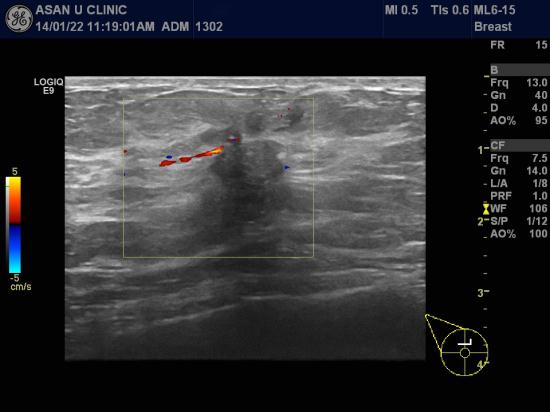

아산유외과 개원 후 61번째 유방암 진단.

갑자기 만져지는 우측 유방의 몽우리로 내원한 60세 여성분입니다.

1.54cm의 유방 종괴를 중심핵생검으로 조직검사하여

침윤성 유관암으로 진단받았습니다.

겨드랑이 림프절에 전이 의심되는 소견이 없어서

1기로 추정되는 임상증례입니다.